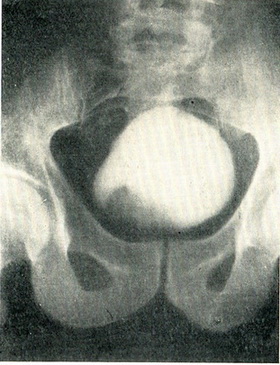

Основним методом діагностики є цистоскопія. При цьому легко виявляється пухлина, визначається її локалізація, розмір і загальний вигляд, а також стан слизової оболонки, що оточує пухлину, і гирл сечоводів. Гілляста новоутворення з довгими ніжними ворсин на тонкій ніжці, дає тінь, оточене незміненою слизовою оболонкою, що є типовим для неинфильтрирующей пухлини (рис. 108). Широке підстава і короткі товсті ворсини пухлини вказують на инфильтрирующий зростання (рис. 109). Бульозний набряк, розширення судин навколо основи пухлини також вказують на інфільтрацію стінки міхура.

![]() Рис. 108. Неинфильтрирующая папілярна пухлина сечового міхура. Цистоскопія. |

Гістологічне дослідження шматочка пухлини, взятого гострою ложечкою через цистоскоп, дозволяє диференціювати пухлину із грануляційною тканиною, туберкульозом або іншими запальними процесами. За даними біопсії далеко не завжди вдається встановити доброякісність або злоякісність пухлини. При цистографії з 10% розчином сергозина на місці пухлини видно дефект наповнення. Якщо контури міхура залишаються при цьому незмінними, то пухлина з великою ймовірністю можна вважати неинфильтрирующей (рис. 111). Якщо поряд з дефектом наповнення нерівні контури міхура, є асиметрія менаду правою і лівою половиною міхура, то в инфильтрирующем характер пухлини можна не сумніватися (рис. 112).

Рис. 111. Неинфильтрирующая папілярна пухлина сечового міхура, дефект наповнення праворуч. Контури міхура не змінені. Цистограмма з 10% сергозином.